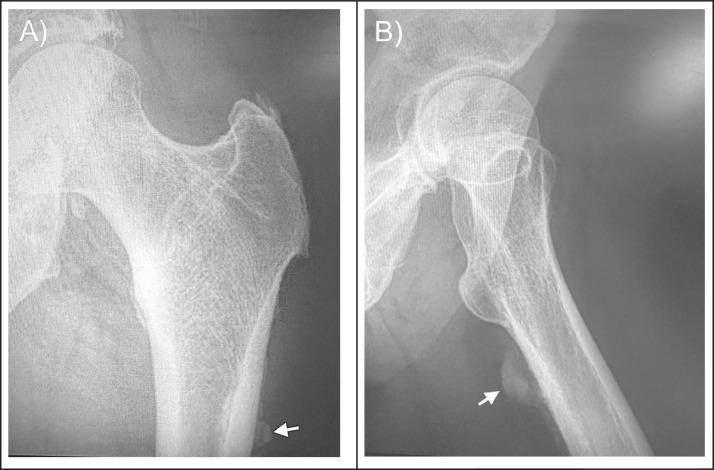

Calcific tendinitis, classified as enthesopathy, is a self-limiting disease that rarely involves the tendons of the gluteus maximus. We discuss a 52-year-old woman with a 1-year history of localized, reproducible posterolateral pain of her left hip, which was previously treated with steroid injection to her left greater trochanteric bursa without significant pain relief. Plain radiography and magnetic resonance imaging of the left hip revealed abnormal edema and calcifications at the insertion of the gluteus maximus tendon to the gluteal tuberosity, corresponding to the area of maximal tenderness on examination. This case report contributes to the growing medical literature for the rare presentation of calcific tendinitis of gluteus maximus insertion and reinforces the importance of the patient history, focused physical examination with special testing, and pertinent imaging for proper diagnosis and management.

钙化性肌腱炎归类为附着点病,是一种自限性疾病,很少累及臀大肌肌腱。我们讨论一位52岁女性,她有1年的左侧臀部局限性、可重复性后外侧疼痛病史,此前曾接受向左侧大转子滑囊注射类固醇治疗,但疼痛未明显缓解。左侧髋关节的X线平片和磁共振成像显示,臀大肌肌腱在臀肌粗隆附着处有异常水肿和钙化,与检查时压痛最明显的区域相符。本病例报告为臀大肌附着处钙化性肌腱炎的罕见表现增加了医学文献资料,并强调了患者病史、重点体格检查及特殊检查以及相关影像学检查对于正确诊断和管理的重要性。